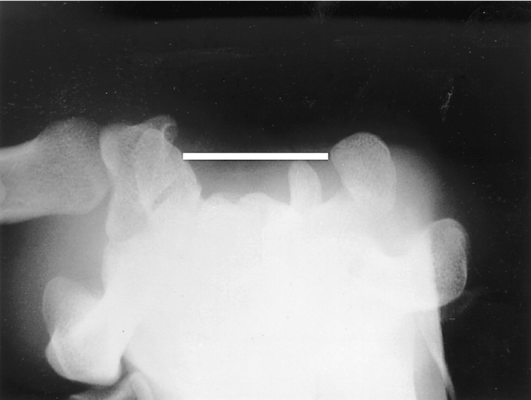

X quang: Chụp X quang cổ tay có thể hữu ích nếu nghi ngờ gãy xương hoặc bệnh thoái hóa khớp.